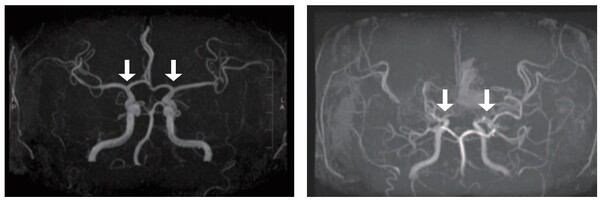

소아 모야모야병 조기 진단 가능성을 높이는 새로운 바이오마커가 발견됐다. 모야모야병 환자의 뇌척수액에서 ‘SLITRK1’ 단백질 발현이 유의하게 증가한 사실을 확인했다. 아울러 뇌경색 발생 및 수술 예후 등 모야모야병의 주요 임상 특성과 연관된 단백질도 확인돼, 난치성 질환인 모야모야...